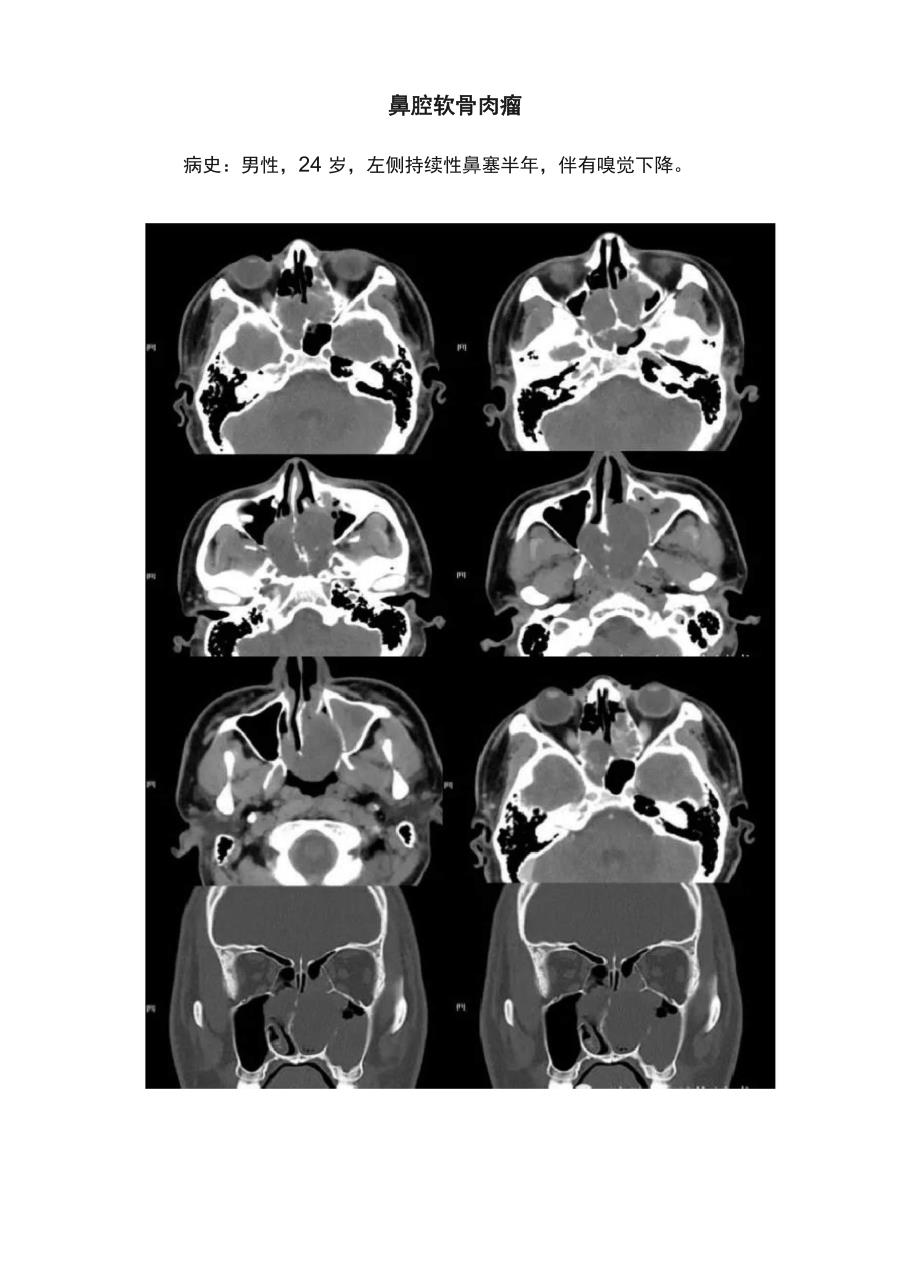

鼻腔软骨肉瘤病史:男性,24 岁,左侧持续性鼻塞半年,伴有嗅觉下降丈体所lib术甬甬雄滞勒:看蚯包柱需业镇3屋加M・幅分童輩样.押务儒爾衣由啟 略鐵・仝取*址下断见iI 粧 危心曲算律吐 詠刻齒隹 孙岸*什住■皐 圭菟 广需PL富M病理会诊结果:鼻腔软骨肉瘤!一、诊断依据软骨肉瘤(chond rosarcoma)是肿瘤细胞具有软骨细胞特征的恶 性肿瘤, 多发生于长骨、骨盆及肋骨, 颅面部较少见, 文献报道发生率<> 可起源于骨、软骨或软组织, 常累及的部位为上颌、下颌及颅底 , 发生 于鼻和眶者少见1、软骨肉瘤的组织学分型颅面部软骨肉瘤绝大多数为原发,仅少数继发于软骨瘤、骨软骨瘤、 软骨黏液纤维瘤、骨纤维异常增殖症、畸形性骨炎等病变分为普通 型(髓内性)、间叶型、去分化型和透明细胞型 4 种类型,其中普通型最 常见间叶型软骨肉瘤:由未分化的间叶细胞和软骨组织构成, 常有明显 血管;起源于骨或骨外结构, 易发生于头颈部, 上、下颌骨是常见骨源部 位,骨外常发生于眼眶和脑膜, 也可起源于鼻黏膜去分化型软骨肉瘤:是指在低度恶性软骨肉瘤周边出现纤维肉瘤、 骨肉瘤和恶性纤维组织细胞瘤等高度间变肉瘤区, 镜下 2种成分界线分 明。

2、临床表现 鼻软骨肉瘤患者主要为进行性鼻阻、流涕、反复鼻衄, 其他包括疼 痛、面部肿胀或麻木、牙痛、嗅觉减退、头痛、突眼、复视、视力下 降、颅神经麻痹等3、典型CT表现软组织肿块内有散在点、结节、环形、斑片状或不定型软骨基质 钙化, 钙化是本病最重要的影像学征象而间叶型软骨肉瘤的钙化形态 更小,密度更淡鼻软骨肉瘤常伴邻近骨质侵蚀或破坏,易侵犯周围结构4鼻眶部普通型软骨肉瘤MRI表现T1WI上多表现为低或等信号T2WI多表现为高信号但信号不均 匀瘤体内散在形态及数量不一的低信号区大致对应CT上所见的软骨 基质钙化增强后多数病例显示轻到中度不均匀强化, 典型者表现为边 缘及间隔明显强化,而内部强化较轻或不强化,外观呈斑驳状或蜂窝状,相应的组织学上显示边缘和间隔由纤维血管构成 ,而内部主要由软骨、 黏液或坏死组织构成5、鼻眶部间叶型软骨肉瘤MRI报道少见,T1WI常表现为低或等信号T2W I多为等信号软骨基 质的钙化常难以显示;增强后呈弥漫性均匀或不均匀的高度强化 ,也缺 乏典型的边缘和间隔强化文献报道部分间叶型软骨肉瘤在MRI上可 显示蛇形流空的血管影,对应组织学上的小细胞区和夹杂在软骨组织 中的血管外皮瘤样区征象。